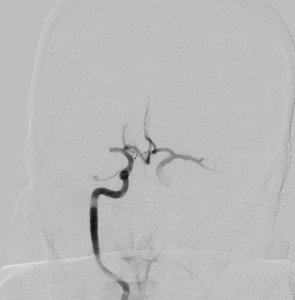

Check out these angiograms of large vessel occlusions from our image database: